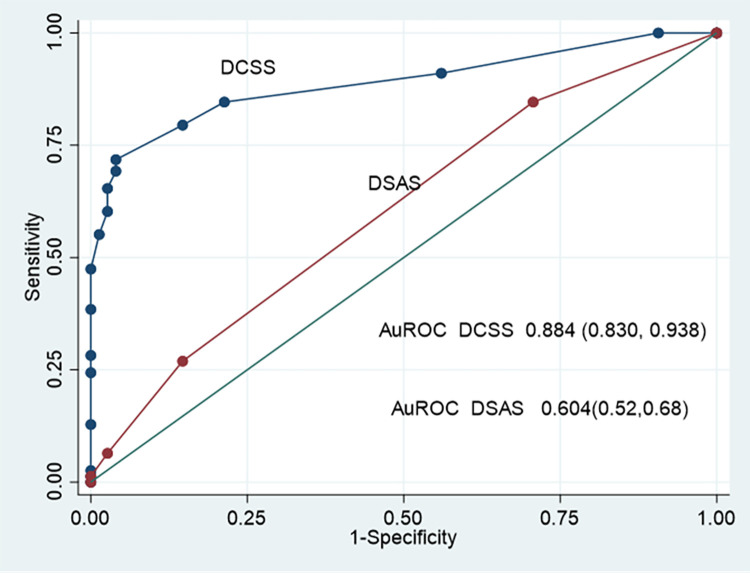

Model performance

The model discrimination performance is demonstrated by the ROC curve of the Difficult CBD stone score (DCSS) model, shown in Fig 2. The area under the receiver operating characteristic curve (AuROC) of the DCSS model revealed an affinity for prediction of 88.39% (95% CI: 0.83, 0.93).

Internal validation was performed by the bootstrap sampling method with 500 replications, which showed constant AuROC 0.884 (95%CI 0.830, 0.938) with model optimism adjusted at AuROC 0.883 (95%CI 0.833, 0.942). The analysis showed acceptable predictive performance.

The ROC curve and AuROC of the DCSS model were compared using the added value concept to an intelligent difficulty scoring and assistance system (DSAS) for endoscopic treatment of common bile duct (CBD) stones that was proposed by Huang et al. [ref. 13] (Fig 5.) The DCSS model’s ability to predict the required EPLBD was 88.78%, which increased from the ability to predict the required EPLBD of DSAS was 46.48% (p <0.001).